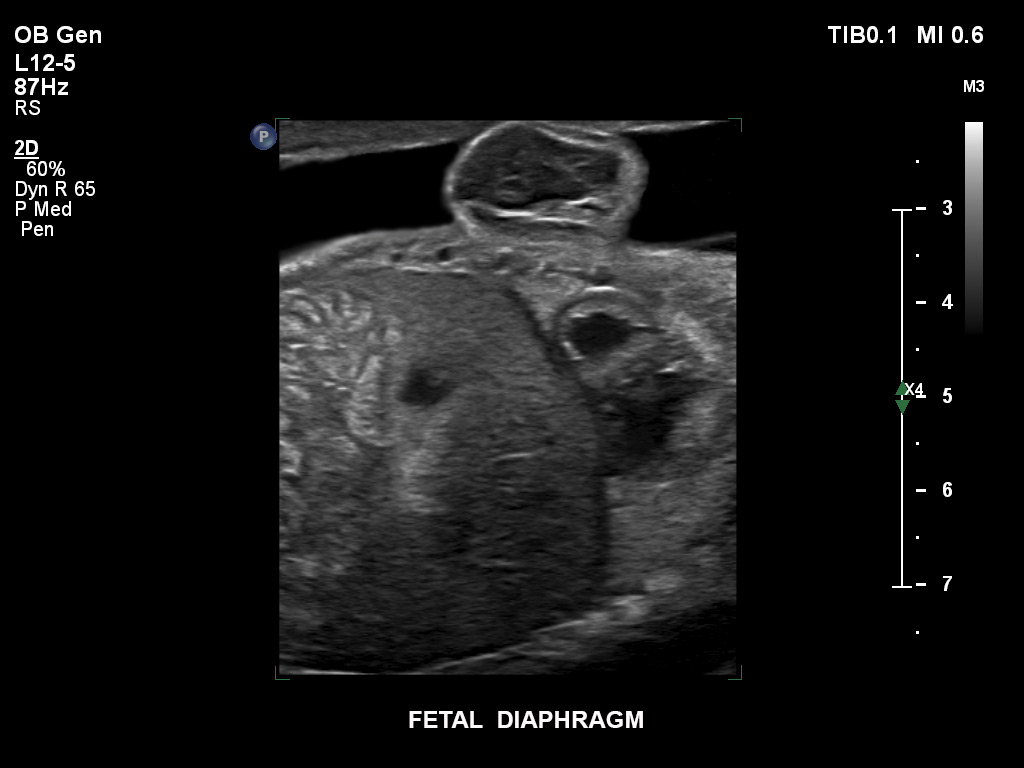

Die EPIQ-Produktreihe mit ausgereiften Schallköpfen erfüllt die Anforderungen auch Ihrer anspruchsvollsten gynäkologischen Untersuchungen und während der gesamten Schwangerschaft.

• C9-2 PureWave-Breitband-Convex-Schallkopf für Hochfrequenz-Bildgebung in der Gynäkologie und der Geburtshilfe, insbesondere für die Untersuchung im Hinblick auf mögliche Anomalien im ersten Schwangerschaftstrimester

• C10-3v PureWave-Breitband-Endo-Convex-Schallkopf, ideal für anspruchsvolle Myom- und komplexe Ovar-Untersuchungen sowie Bildgebung im ersten Schwangerschaftstrimester